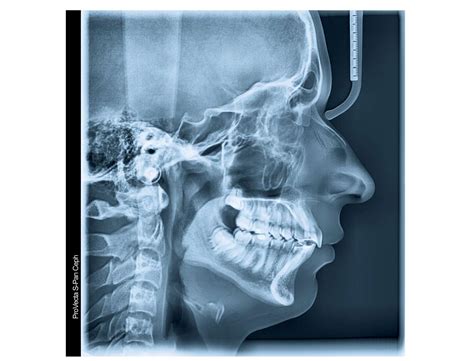

Orthodontic treatment has evolved significantly over the years, with advancements in technology playing a crucial role in improving diagnostic accuracy and treatment outcomes. One of the most essential tools in this field is the Cephalometric X Ray. This imaging technique provides a comprehensive view of the skull and facial bones, enabling orthodontists to plan and execute treatments with precision. This blog post delves into the importance of Cephalometric X Rays, their applications, and the detailed process involved in obtaining and interpreting these images.

A Cephalometric X Ray is a specialized type of radiograph used to analyze the relationship between the teeth and the jaw. It provides a two-dimensional view of the skull, focusing on the facial bones and teeth. This imaging technique is invaluable for diagnosing and treating various orthodontic conditions, including malocclusions, jaw discrepancies, and facial asymmetries.

The patient’s head is positioned so that the Frankfort plane (a line drawn from the top of the ear canal to the bottom of the eye socket) is parallel to the floor. This ensures that the X-ray beam passes through the skull at the correct angle, providing an accurate image of the facial bones and teeth.